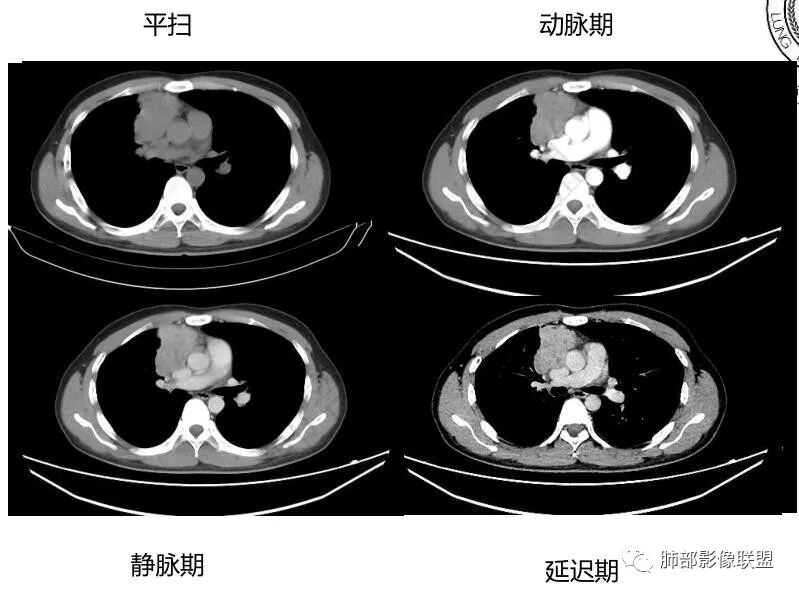

中青年男性,前纵膈偏右侧软组织肿块,形态不规则,有分叶,密度均匀,增强病灶轻中度强化,内部可见低或无强化区域,病灶与血管周围间隙分界不清晰,考虑恶性或交界性肿瘤,胸腺类癌>生殖细胞瘤>淋巴瘤。

青年男性,前上纵隔占位,渐进强化,坏死不明显,nse稍高,首先考虑类癌,鉴别精原,内胚窦瘤,需要结合实验室检查HCG,AFP等

中年男性,胸痛,既往健康,前上纵隔软组织肿块,形态不规则,密度不均,没有血管包埋及受侵征象,呈不均匀强化,考虑胸腺瘤,鉴别淋巴瘤,精原细胞瘤,胸腺癌

前纵隔右侧见大肿块,边缘清,同侧内乳动脉增粗,渐进性延迟强化明显,强化密度不均匀,中心见偏低密度灶,上腔静脉内后侧推压移位(提示肿块质地偏硬),副神经节瘤,与巨淋巴细胞增生症鉴别。

青年男性,咳嗽,右上前纵隔不规则肿块,分叶,上腔静脉受压,内乳动脉增粗,延迟强化明显,坏死不明显,考虑来源纵隔,胸腺瘤,淋巴瘤,神经源性肿瘤都可以,比较年轻,猜个淋巴瘤吧。神经源性肿瘤代排。

青年男性,前纵隔软组织肿块,偏右侧生长,边缘多发分叶,包绕临近血管生长,增强后轻度强化,并呈渐进性,可见点状坏死,考虑胸腺瘤,鉴别淋巴瘤,生殖细胞肿瘤,巨淋巴结增生症

青年男性,前纵隔偏右侧软组织肿块,密度均匀,分叶,渐进性不均匀强化,可见点状坏死,考虑胸腺瘤,鉴别生殖细胞肿瘤,淋巴瘤,CD。

青年男性,前纵隔偏右侧肿块,分叶,与邻近血管分界不清,上腔静脉受压,不均匀渐进强化,点状坏死,考虑胸腺瘤,鉴别胸腺类癌

男性32岁前纵隔偏右侧见一不规则软组织影,边缘毛刺,呈分叶征,同侧内乳动脉增粗,延迟性强化,内见条状分隔影,考虑胸腺瘤(B1、2,临界年龄段,分隔有些提示倾向),NSE轻度升高,中度强化,类癌代排。内胚窦及精原等生殖细胞肿瘤影像不符合,建议结合实验室检查

年轻男性,NSE稍高,前纵隔偏右侧不规则实性肿块,平扫密度均匀,增强渐进性不均匀强化,内见低密度区,似见条样分隔。考虑为胸腺瘤,建议实验室检查HCG,AFP等鉴别生殖细胞肿瘤

青年男性,前上纵隔占位,偏侧生长,边缘不规则,可见分叶及分隔,内见少量无强化低密度区,常规考虑胸腺瘤,NSE稍偏高一点,会不会是实验室误差?

前纵隔右侧不规则软组织肿块,边缘欠清,增强渐进性强化,内见星状无强化分隔,部分分隔延迟强化,青年男性,首先考虑精原细胞瘤,鉴别胸腺瘤,NSE轻度升高,类癌也需鉴别!

前纵隔肿块,轻度分叶,边界不清楚,延迟强化,可见分隔,倾向恶性或具有一定侵袭性病灶。